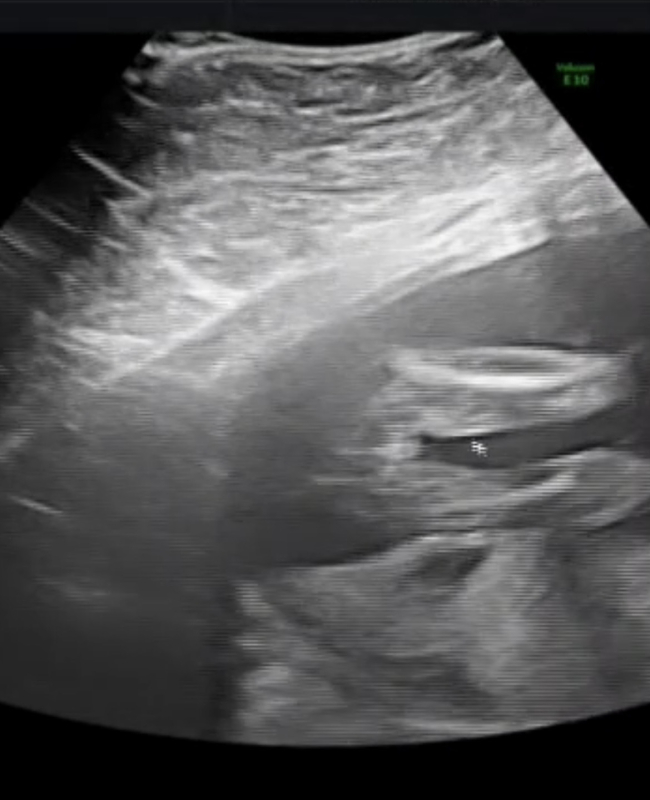

実際にエコーで拝見しているわけではないので、お写真からですと、なかなかはっきりとしたことはお話しできませんが、その時のお子さんの位置や向きによってもうまく見えたり見えなかったりします。お写真からですと、間違えて見えてしまうこともよくあります。せっかくご相談いただきましたのに、お役に立たず申し訳ありませんが、医師もまだ確定できないお伝えしているのであれば、はっきりとは見えていないのかもしれませんね。また再度健診の際にご確認なさってくださいね。